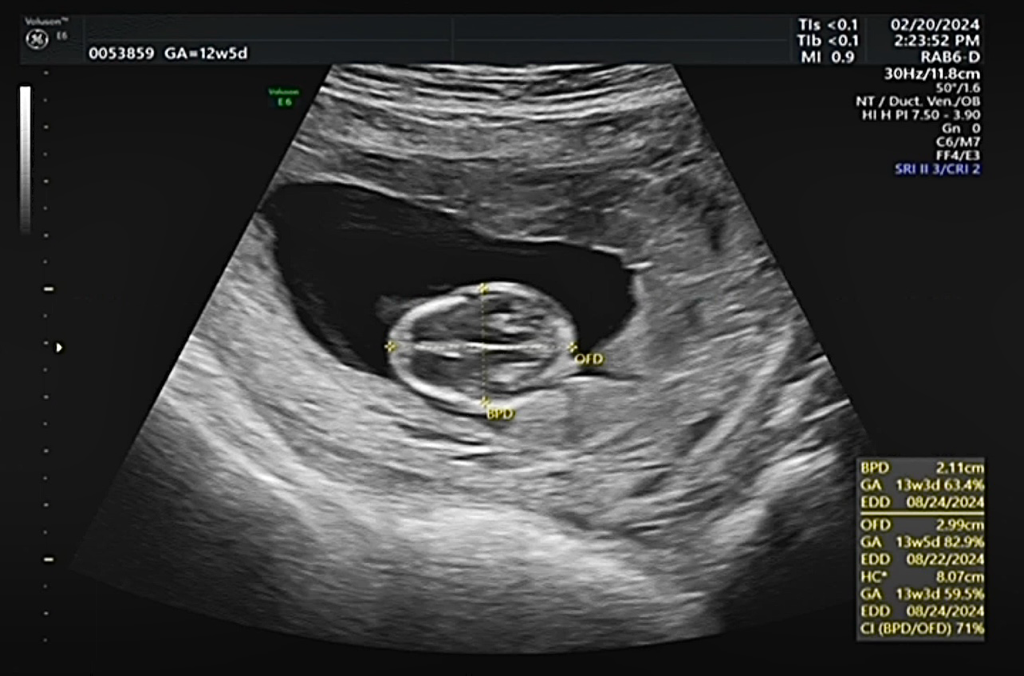

BPD雙頂骨徑21.1mm 13w3d

OFD頭前後徑29.9mm 13w5d

AC腹圍 61.9mm 13w0d

CRL頭臀徑68mm 13w1d

FL股骨長8.2mm 12w3d

上面這是我2/20照高層次出來的數據

我要推算受孕日 想知道應該要以哪個週數會比較準

OFD的週數就是獅子寶寶了 真的很想推受孕日

因為醫生跟我說寶寶在肚子 有時候可能身體稍微捲曲沒有打直 長度會有一點差

13週看頭會比較準嗎

(我知道都會有差別但想知道看什麼是最準的當天只有超音波技師來不及問醫生

然後那些周數後面的%數是什麼意思